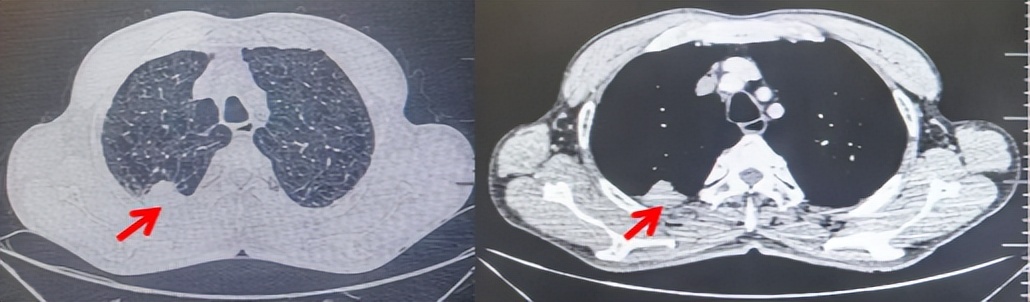

69岁男性,无糖尿病、高血压、心脏病等基础疾病,无吸烟、饮酒史,无肿瘤家族史。2023.06.07行胸部CT检查:右肺上叶胸膜下见肿物影,大小约33mm×22mm,边缘可见分叶,考虑恶性病变可能性大,双肺间质改变(如图1)。2023.06.14行“单孔胸腔镜下右肺上叶切除、肺门及纵隔淋巴结清扫、胸膜粘连松解术”;术后病理:(右肺上叶)腺癌(低分化,实体型占60%,不良腺体占40%),局灶伴神经内分泌标记表达(CD56、Syn),可见STAS及胸膜侵犯,未见确切神经侵犯及脉管内癌栓;(气管切缘)净;(淋巴结)未见转移癌0/26(2组0/2;4组0/6;7组0/2;对侧7组0/8;10组0/2;11组0/3;12组0/2;13组0/1)。术后分期pT2aN0M0 IB期,术后NGS基因检测:无驱动基因突变,PD-L1(22C3)TPS<1%。术后定期复查。

2024.11.19患者出现右侧胸痛,复查胸部CT检查示右侧胸膜肿物,大小约31mmX24mm,右侧4、5肋骨骨质破坏,考虑转移(如图2)。建议患者穿刺活检取病理明确诊断,患者拒绝,经MDT会诊后结合影像学表现及病史考虑为胸膜转移,肋骨转移,分期为rT0N0M1a IVA期,DFS仅仅17个月。2024.12.05起行信迪利单抗联合培美曲塞+卡铂方案治疗4周期,复查胸CT评效PR(如图3)。之后给予信迪利单抗+培美曲塞维持治疗6周期,期间复查CT评效PR(如图3)。目前信迪利单抗+培美曲塞维持治疗中,截止至目前PFS约为8个月,治疗期间未出现明显毒副反应。

图1:患者手术前(2023.06)胸部CT肺窗及纵隔窗

图2:患者胸膜及肋骨转移(2024.11)胸部CT肺窗、纵隔窗及骨窗

图3:患者免疫联合化疗治疗后胸部CT,(A、B)图展示信迪利单抗联合培美曲塞+卡铂治疗

4周期(2025.02)疗效,(C、D)图展示信迪利单抗+培美曲塞维持治疗6周期(2025.07)疗效